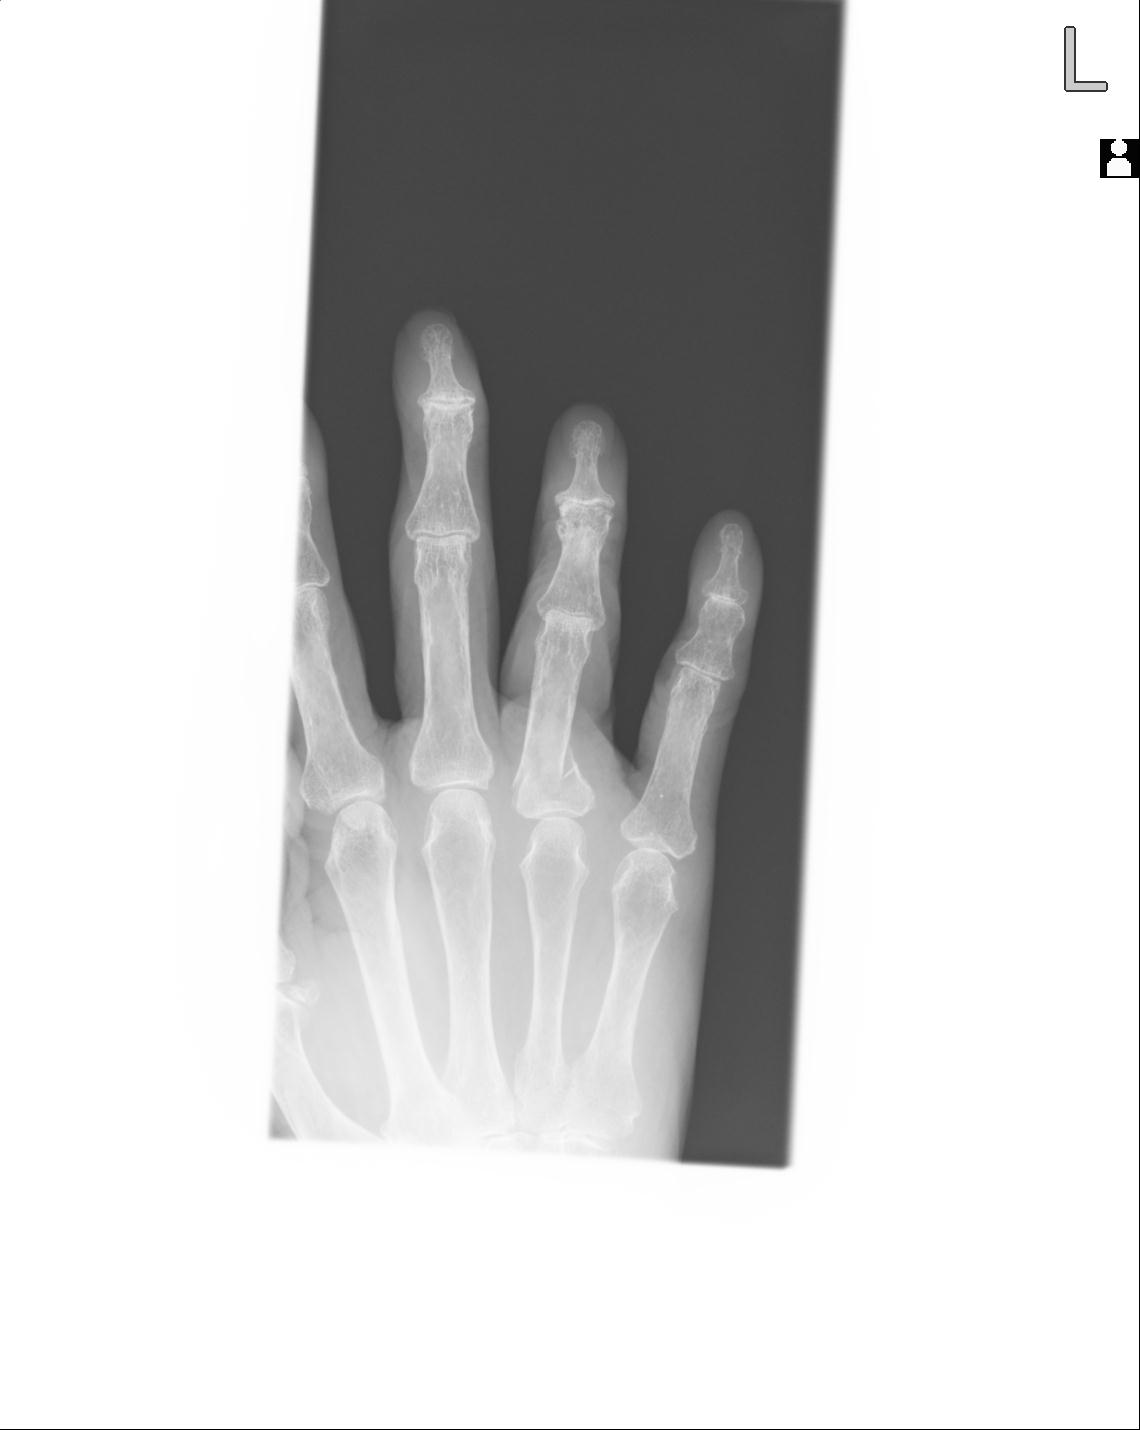

102860 1/21 (4R) 1/26 (4R) 3/15 左手 2R 91歳女性 左環指中節骨

20857 1/11 左手 3R 1/19 4R 55歳男性 小指中節骨骨折

102766 1/5 1/12 左手関節 4R 28歳男性 左橈骨遠位端

50435 1/4 1/15 手関節 4R 17歳女性 右橈骨遠位端

102739 12/30 1/5 左手関節 4R 92歳女性 橈骨遠位端

101290 1/4 5/21 5/20 手関節 2R 17歳男性 橈骨遠位端